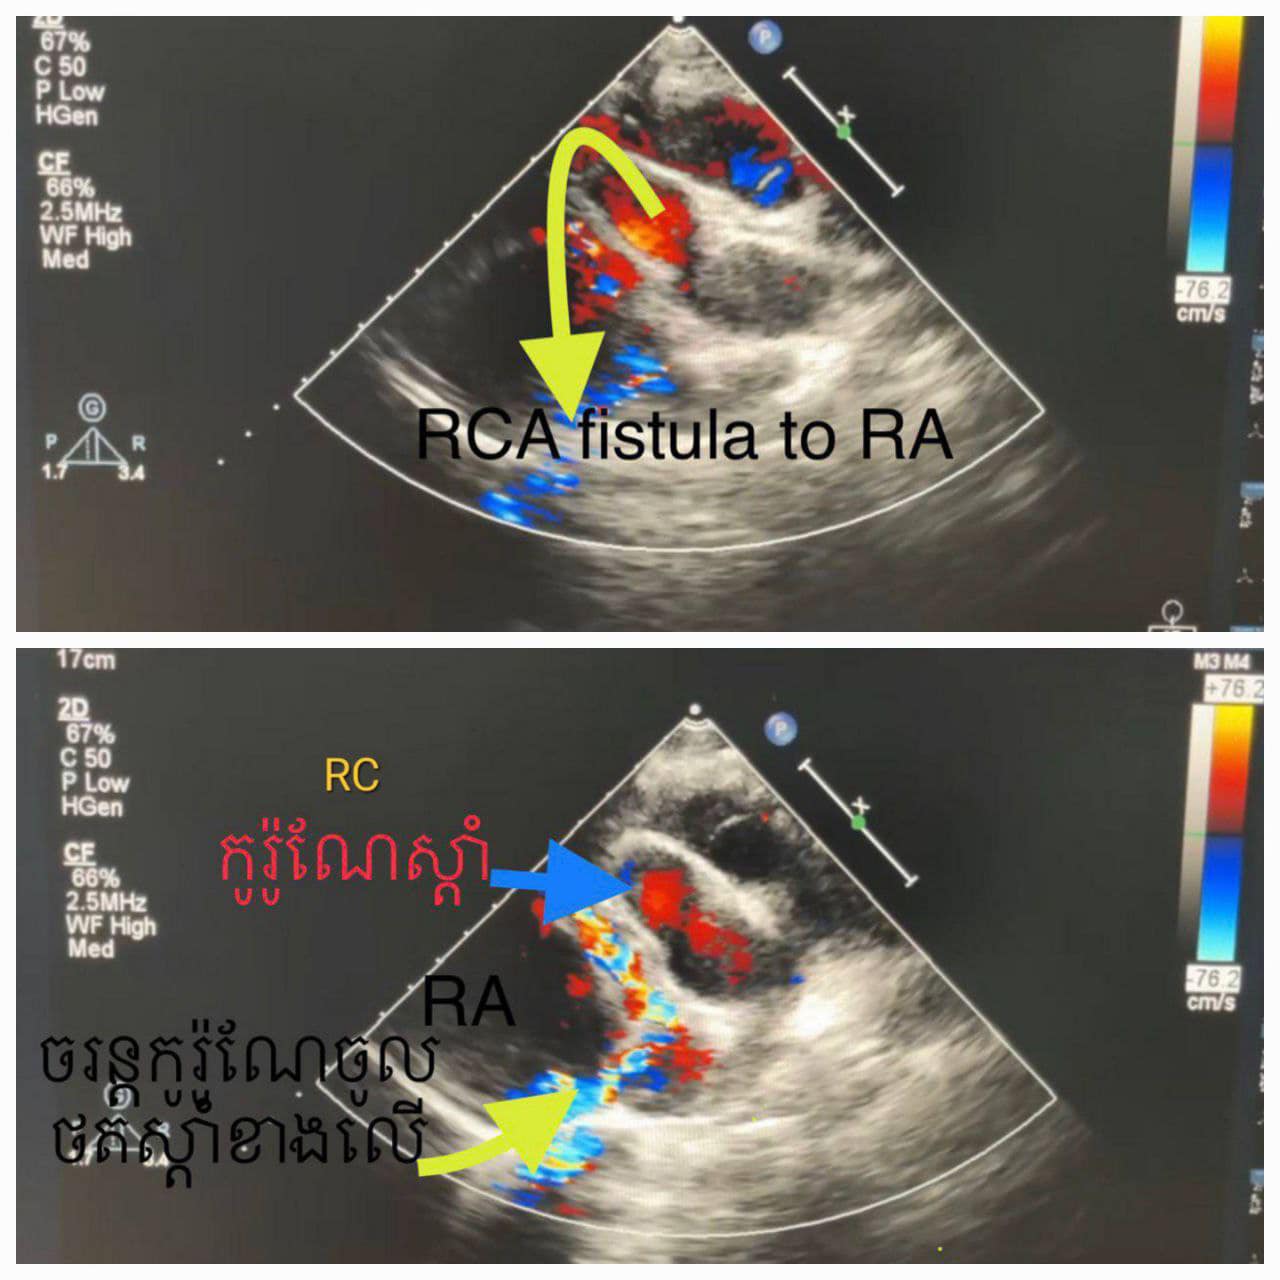

ខេត្តសៀមរាប៖ នៅថ្ងៃទី២៧ ខែមីនា ឆ្នាំ២០២៣ យោងតាមការចុះផ្សាយរបស់ មន្ទីរពេទ្យគន្ធបុប្ផា បានឱ្យដឹងថា ក្មេងប្រុស អាយុ១៣ឆ្នាំ មកពីស្រុកជើងព្រៃខេត្តកំពង់ចាម ដោយអាការៈចុកទ្រូងខ្លាំងរយៈពេល៥ថ្ងៃ ពេលមកដល់មន្ទីរពេទ្យជ័យវរ្ម័នទី៧ គ្រូពេទ្យឯកទេសផ្នែកបេះដូងបានធ្វើរោគវិនិច្ឆ័យយ៉ាងច្បាស់លាស់ថាជាការរីកសរសៃកូរ៉ូណែខាងស្តាំដោយចរន្តឈាមកូរ៉ូណែខាងស្តាំឆ្លងចូលថតបេះដូងស្តាំខាងលើ( RCA fistula to RA)។

ដូចនេះហើយក្រុមវេជ្ជបណ្ឌិតឯកទេសផ្នែកបេះដូងយើងបានរៀបចំដាក់កម្មវិធីបាញ់ភ្ជិតអោយក្មេងប្រុសម្នាក់នេះដោយបច្ចេកទេសទំនើបបំផុតមួយ catheterization to close RCA fistula to RA by vascular plug ប្រកបដោយភាពជោគជ័យ។